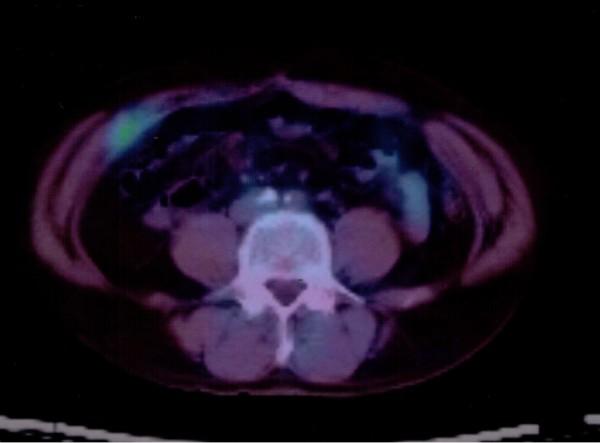

Metastasis to the abdominal wall including port sites after laparoscopic surgery for colorectal cancer is rare. Resection of metastatic lesions may lead to greater survival benefit if the abdominal wall metastasis is the only manifestation of recurrent disease. A 57-year-old man, who underwent laparoscopic surgery for advanced mucinous adenocarcinoma of the cecum 6 years prior, developed a nodule in the surgical wound at the lower right abdomen. Although tumor markers were within normal limits, the metastasis to the abdominal wall and abdominal cavity from the previous cecal cancer was suspected. An abdominal computed tomography scan did not provide detective evidence of metastasis. (18)F-fluorodeoxyglucose positron emission/computed tomography ((18)F-FDG PET/CT) was therefore performed, which demonstrated increased (18)F-fluorodeoxyglucose uptake (maximum standardized uptake value: 3.1) in the small abdominal wall nodule alone. Histopathological examination of the resected nodule confirmed the diagnosis of metastatic mucinous adenocarcinoma. Prognosis of intestinal mucinous adenocarcinoma is reported to be poorer than that of non-mucinous adenocarcinoma. In conclusion, this case suggests an important role of (18)F-FDG PET/CT in early diagnosis and decision-making regarding therapy for recurrent disease in cases where a firm diagnosis of recurrent colorectal cancer is difficult to make.

腹壁转移包括结直肠癌腹腔镜手术后的端口部位转移较为罕见。如果腹壁转移是复发性疾病的唯一表现,切除转移病灶可能会带来更大的生存获益。一位 57 岁男性,6 年前因盲肠高级黏液性腺癌接受了腹腔镜手术,在右下腹部的手术伤口处出现了一个结节。尽管肿瘤标志物在正常范围内,但仍怀疑是先前盲肠癌转移至腹壁和腹腔。腹部 CT 扫描未提供转移的探测证据。因此进行了氟代脱氧葡萄糖正电子发射/计算机断层扫描(18F-FDG PET/CT),结果显示小腹部结节单独摄取增加(18F-FDG 最大标准化摄取值:3.1)。切除结节的组织病理学检查证实了转移性黏液性腺癌的诊断。肠黏液性腺癌的预后比非黏液性腺癌差。总之,本例提示在难以明确诊断复发性结直肠癌的情况下,18F-FDG PET/CT 在早期诊断和治疗复发性疾病方面具有重要作用。